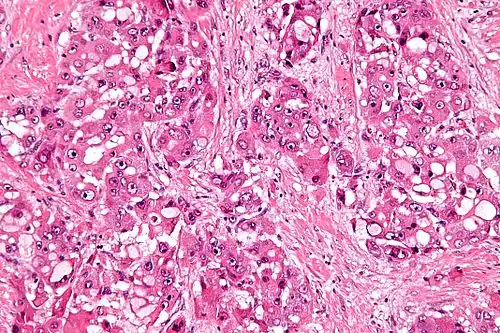

Intermed. mag. -

The histopathology of FLC is characterized by laminated fibrous layers, interspersed between the tumor cells. Cytologically, the tumor cells have a low nuclear to cytoplasmic ratio with abundant eosinophilic cytoplasm.[1] Tumors are non-encapsulated, but well circumscribed, when compared to conventional HCC (which typically has an invasive border).